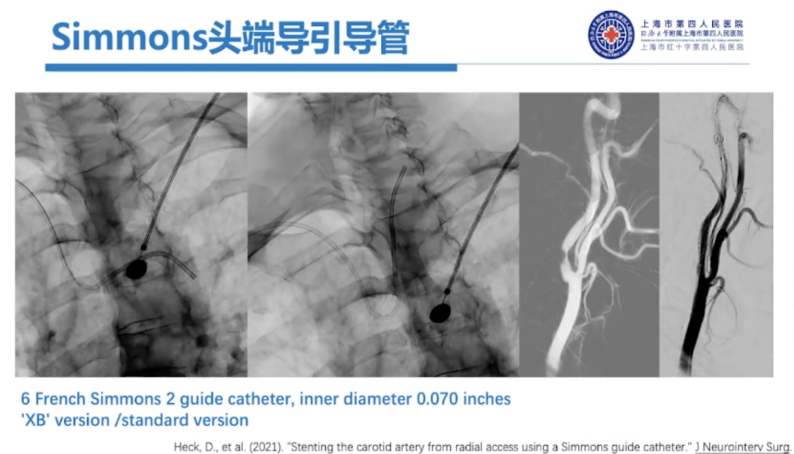

目前市面上有一款Sim头端的导引导管,可同时完成入路建立和弓上超选。但其在实际应用中会存在一些问题:头端长度固定,如果想超选至更远处,治疗颅内病变就会遇到问题。

常规Sim造影导管到位时,由于反向弯的作用,导管会往前滑,我们也会让它顺应血管到达更远的位置,此时导管膝部和颈动脉弯曲角度是合适的。如果用这样Sim头端的导引导管去建立通路就会存在风险,它不能够在任意位点达到稳定的位置,有可能头端还会顶到血管壁,造成夹层。

器械选择:6F通桥银蛇DA远端通路导引导管/中间导管/长鞘+125cm 5F Sim II导管,这是我们最常用的组合。

选用长鞘的情况下,因为导管较短,有的时候用100cm Sim II配合80cm的长鞘也是可以完成入路建立的,但大部分情况下,我们需要125cm Sim II。在没有现成Sim II中心可用125cm 多功能管手工塑形。